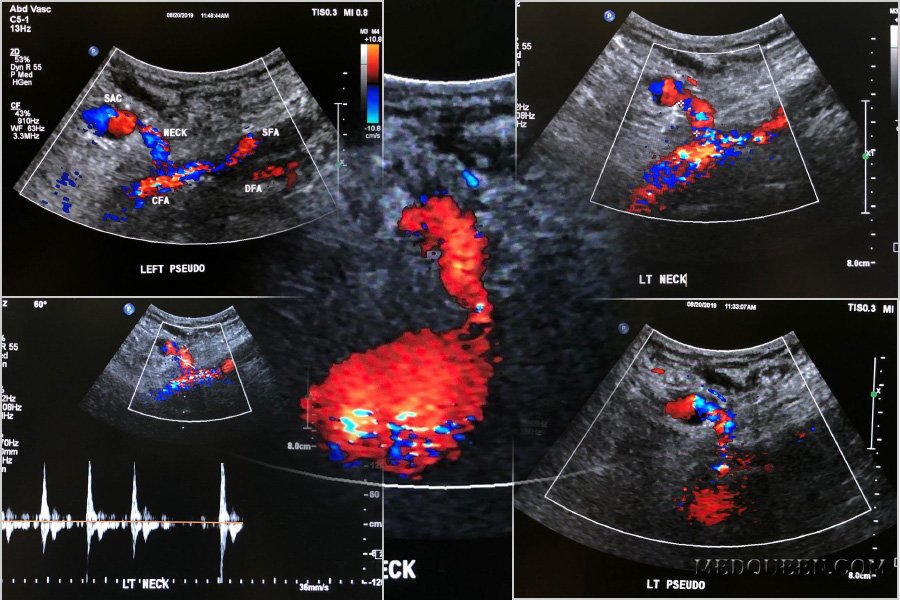

Под понятием «ложная аневризма» следует подразумевать скопление крови вне сосуда, сообщающееся с артерией через шейку, что приводит к завихрению кровотока внутри образования с характерной картиной на цветовой допплерографии. Исследование пульсовых волн ложной аневризмы показывает приносящий кровоток высокой скорости в момент систолы и длительный отток на протяжение всей диастолы (фото 1).

УЗИ: Ложная аневризма общей бедренной артерии

Фото 1. Ложная аневризма общей бедренной артерии. А – цветовая допплерограмма паховой области, выполненная в поперечной проекции: визуализируется общая бедренная артерия (CFA), стрелкой отмечена шейка аневризмы, указателями отмечена ложная аневризма, локализованная спереди, в которой наблюдается типичная картина «инь-янь» красного и синего цвета, что обусловлено завихрением кровотока. В – спектральная допплерограмма шейки ложной аневризмы подтверждает кровоток в обе стороны («туда-сюда»).

Допплерографическое исследование позволяет диагностировать ложную аневризму при обнаружении в ее шейке потока по типу «туда-сюда» (компонент «сюда» обусловлен расширением полости ложной аневризмы по мере вхождения в нее крови в систолу; компонент «тужа» отмечается в диастолу, когда кровь, накопившаяся во время диастола, возвращается обратно в артерию (фото 1).

Признаки ложной аневризмы на цветовой допплерографии характеризуются классическим двунаправленным потоком внутри капсулы аневризмы при каждом сердечном цикле – симптом «инь-янь».